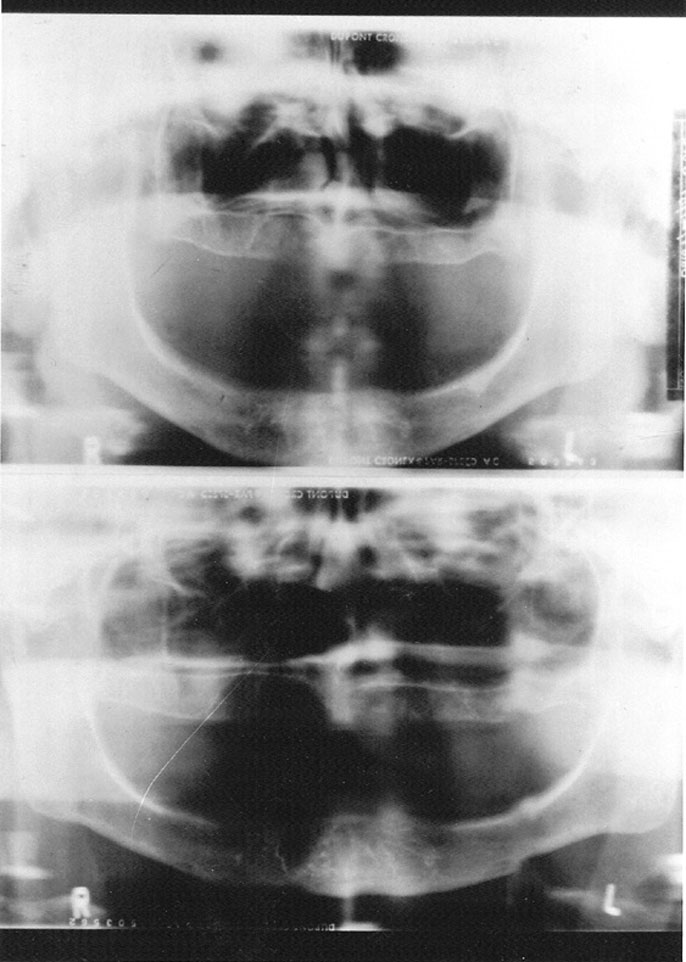

Figure 24. Panoramic error - patient too far forward.

Figure 24

Focal Trough

Panoramic radiographs blur out some anatomic structures in order to detail others. The U-shaped area where the maxilla and mandible are the sharpest is the image layer or focal trough. Image sharpness within the trough is determined by the position of the object in respect to the x-ray source and the film plane as it rotates around the axis or center of rotation. While different x-ray ma­chines have different trough sizes and shapes, there are several general statements that can be made about all panoramic exams: 1) As the size of the focal trough increases, image sharpness decreases. 2) Image magnification and blurred margins increase more rapidly medially than laterally to the focal trough. 3) Trough thickness is directly related to acceptable image blurring. The thicker the trough, the more the image will be blurred.

The focal trough concept is used to prevent superimposition of extraneous structures which would impede clear view of the dental arches, and allow the clinician to view a discrete, selected image field. Unfortunately, one of the disadvantages of this concept is the exclusion of structures that may reveal diagnostically important information. For example, supernumerary teeth or other dental pathosis lying outside the focal trough may not visualize clearly enough for diagnosis.

Conversely, this same panoramic quirk could suggest the presence of a condition that did not really exist. For example, if the apices of the mandibular incisors were missing, as they are in Figure 24, the clinician could suspect external resorption. In this particular case, further examination with selected periapical films confirmed that the patient had normal, pathology-free dentition. The incisal apices had not visualized on the panograph because the operator had positioned the patient slightly too far forward for the apices to fall within the focal trough.